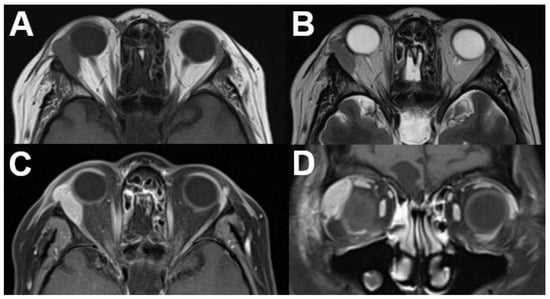

3.1.1. Retinoblastoma

- Rauschecker, A.M.; Patel, C.V.; Yeom, K.W.; Eisenhut, C.A.; Gawande, R.S.; O’Brien, J.M.; Ebrahimi, K.B.; Daldrup-Link, H.E. High-resolution MR imaging of the orbit in patients with retinoblastoma. Radiographics 2012, 32, 1307–1326. [Google Scholar] [CrossRef]

- Lemke, A.J.; Kazi, I.; Mergner, U.; Foerster, P.I.; Heimann, H.; Bechrakis, N.; Schuler, A.; von Pilsach, M.I.; Foerster, M.; Felix, R.; et al. Retinoblastoma—MR appearance using a surface coil in comparison with histopathological results. Eur. Radiol. 2007, 17, 49–60. [Google Scholar] [CrossRef]

- Razek, A.A.; Elkhamary, S. MRI of retinoblastoma. Br. J. Radiol. 2011, 84, 775–784. [Google Scholar] [CrossRef]

- de Graaf, P.; Göricke, S.; Rodjan, F.; Galluzzi, P.; Maeder, P.; Castelijns, J.A.; Brisse, H.J. Guidelines for imaging retinoblastoma: Imaging principles and MRI standardization. Pediatr. Radiol. 2012, 42, 2–14. [Google Scholar] [CrossRef]